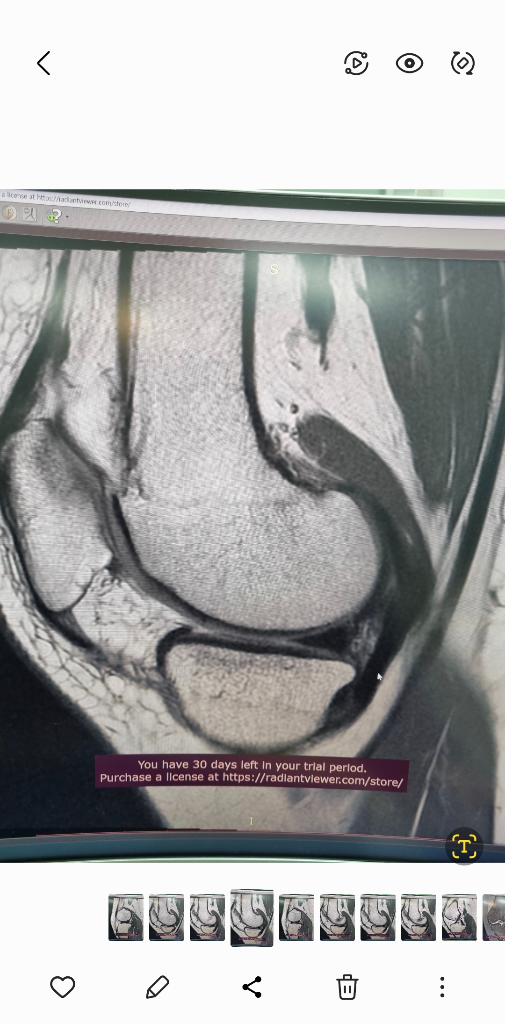

1. 추벽이 아닙니다.

2. 슬개골 관절면에 외상으로 인한 골수부종입니다.

3. 관절면 손상여부는 첨부해주신 영상만으로 알 수 없습니다